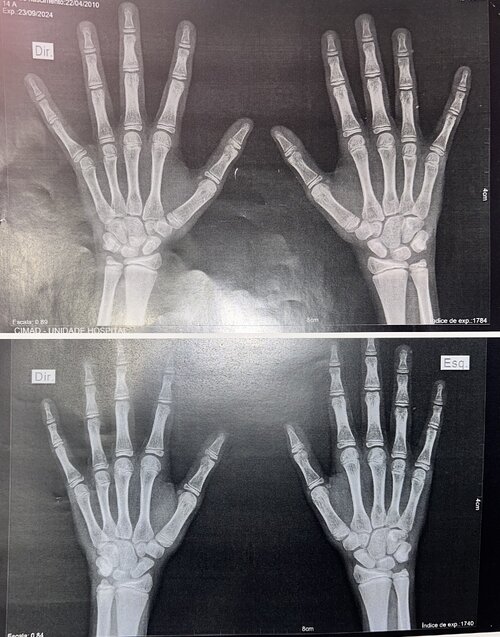

Bone age is around 13–13.6 and hasn’t changed since last year, but my doctor said that’s actually good.

Bone age is around 13–13.6 and hasn’t changed since last year, but my doctor said that’s actually good.